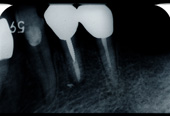

■症例写真

歯周病により溶けてしまった骨を再生造成し補正します。